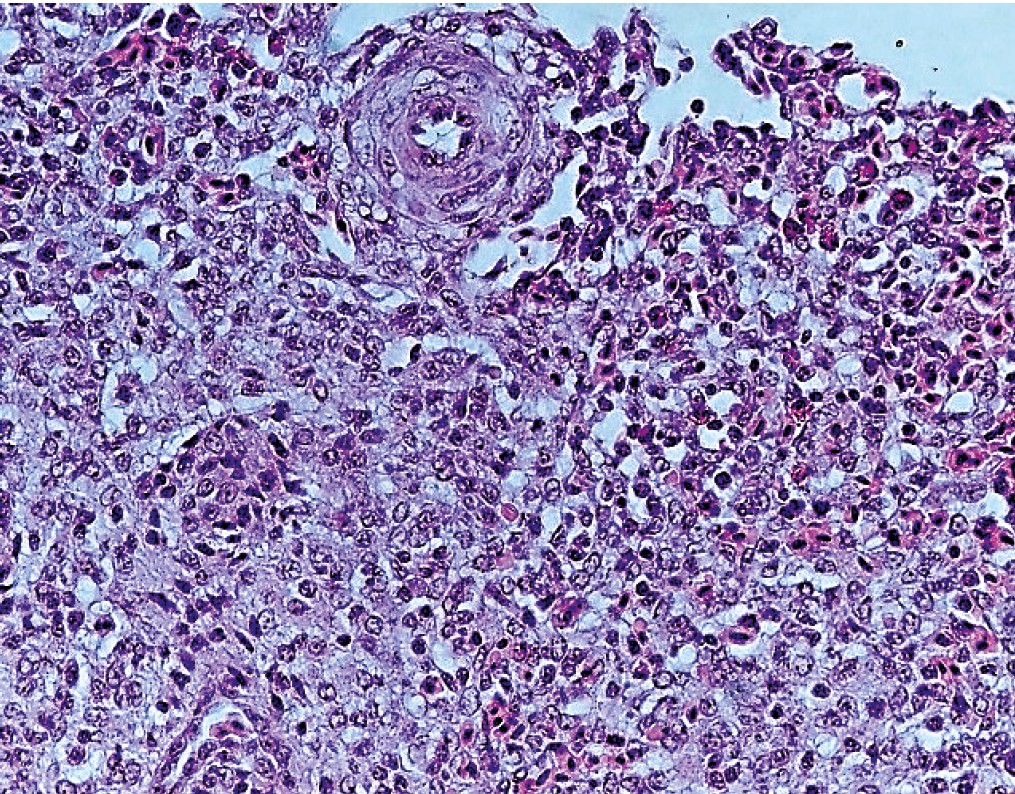

In general, the initiation and development of pathogenetic mechanisms are mediated by decrease in phagocytic function of leukocytes, secretion of acute phase proteins and cytokines, development of septicemia and purulent- inflammatory processes. With prolonged persistence of microorganisms, signs of accidental transformation of thymus, atrophy of bursa of Fabricius, hyperplasia of cells of esophageal follicles, Meckel’s diverticulum of jejunum, cecal lymphoid follicles, and spleen developed. Caryolysis of red blood cells was reliably often observed in areas of emptying of red pulp, and oxyphilic inclusions of granular form were detected in the cytoplasm of red blood cells. The development of pathological processes according to the type of delayed hypersensitivity reaction was accompanied by bacterial embolism of vessels, large cell hyperplasia of lymphadenoid tissue, increase in the number of histiocytes, megakaryocytes. Areas of lysis of red blood cells and clusters of diffusely located hemosiderin granules in parenchyma of spleen and lumen of blood vessels were revealed (Fig. 2).

Fig. 2. Spleen of Chicken infected with bacteria P. aeruginosa. Hematoxylin and eosin. Magnification: 10 × 20, H604 Trinocular Unico, USA

It was found that the relative area of red pulp increased and the relative area of white pulp decreased. There was increase in the total area of reactive centers of white pulp. In areas of compaction and inflammation, cooperative interaction of leukocytes was represented mainly by population of B-lymphocytes and macrophages. Direct correlations (r = 0.89) were noted between indicators of increase in the number of Th1 lymphocytes and hypersecretion of immunoglobulins. A significant increase in the size of lymphoid follicles was established, lymphocytes around the central artery were sparsely located, pyknosis and karyorrhexis of lymphocytes, necrosis of reactive centers were observed. As a rule, areas of sinus desolation, giant macrophages were detected, signs of perivascular reticuloendothelial hyperplasia developed.